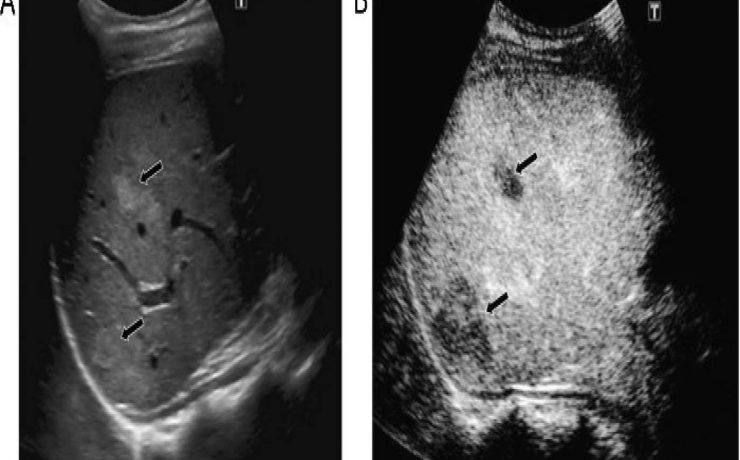

El diagnóstico de tumores ováricos durante el embarazo es cada vez más frecuente como consecuencia del mayor uso rutinario del ultrasonido desde etapas tempranas de la gestación. Si bien la frecuencia sigue siendo baja en relación con otras neoplasias asociadas al embarazo, se reporta una incidencia menor de 5%. Casi